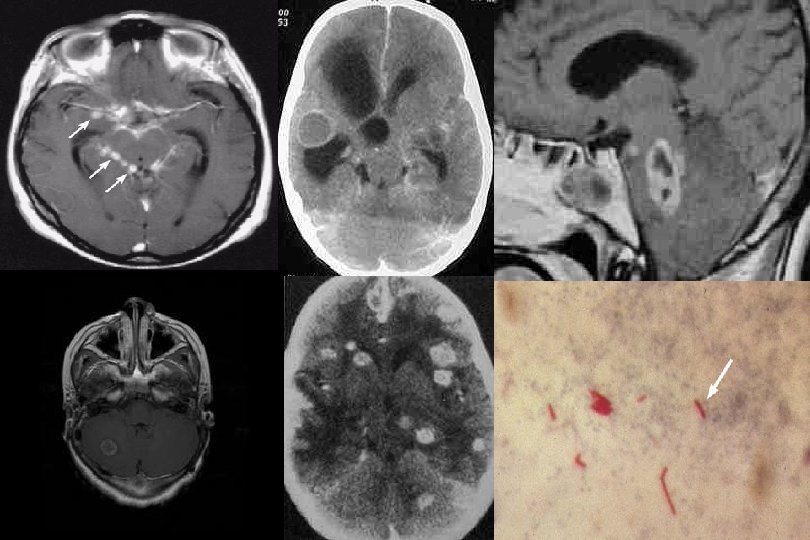

Subakut/kronik menenjit l İnfeksiyonlar: – Tüberküloz – Spiroket hastalıkları(sifiliz, Lyme hastalığı) – Bruselloz – Mantar menenjitleri • Cryptococcus neoformans, Aspergillus, Candida Toxoplasmosis,

Tuberküloz l l Yavaş seyirli Temas, PPD(+)’liği, immün baskılanma Prodrom 2 -4 hafta Menenjit, vaskülit , yer kaplayan lezyon (tüberkülom) belirtileri görülür – – Ateş Bilinç değişikliği Hemipleji, parapleji Göz sinirleri tutulumu